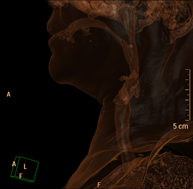

- Laryngeal CT

Radiological test that provides high definition anatomical images of the larynx using CT (Computed Tomography) equipment. Indicated for: sudden or chronic aphonia, respiratory distress.

- Cervical spine CT

Radiological test that provides high definition anatomical images of the cervical vertebrae using CT (Computed Tomography) equipment. Indicated for: cervical pain without/with irradiation to the arms, trauma.